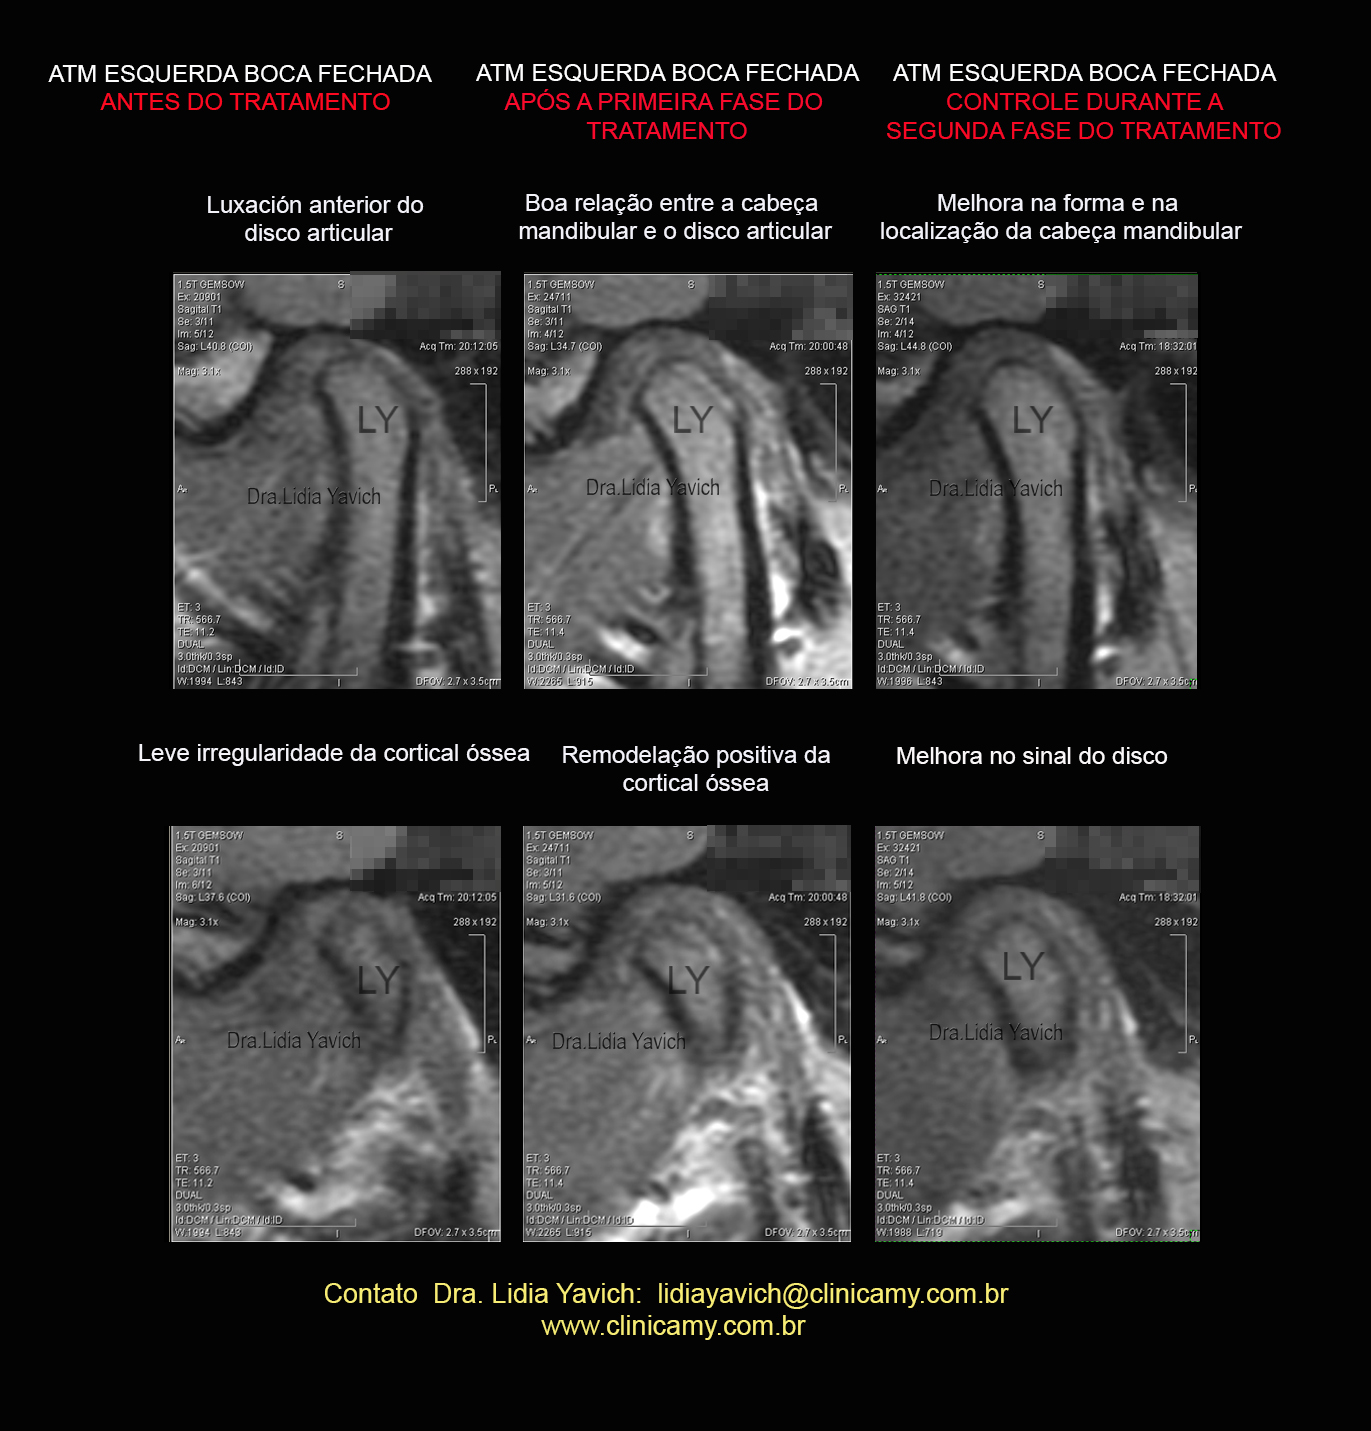

Comparação dos cortes sagitais da RNM da ATM esquerda boca fechada antes e após a primeira fase do tratamento.

Observar a boa relação entre a cabeça mandibular e o disco articular.

Observar a remodelação positiva da cortical óssea.

47 3 ATM ESQUERDA

Comparação dos cortes sagitais da RNM da ATM esquerda boca fechada , após a primeira fase do tratamento e no controle da segunda fase do tratamento ainda não concluído.

Nesta imagem temos uma terceira RNM que não foi apresentada no Congresso da IAO.

As estruturas continuam melhorando.